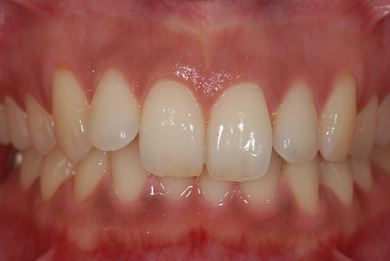

インプラントの症例写真 IMPLANT

インプラント治療

| 主訴 | 銀歯がはずれた奥歯にひびが入っており、抜歯しなければいけないため、インプラントの治療相談を希望。 | ||||||||||||||||||||||||||||||||

| 治療内容 | インプラント1本、メタルボンドセラミック1本 | ||||||||||||||||||||||||||||||||